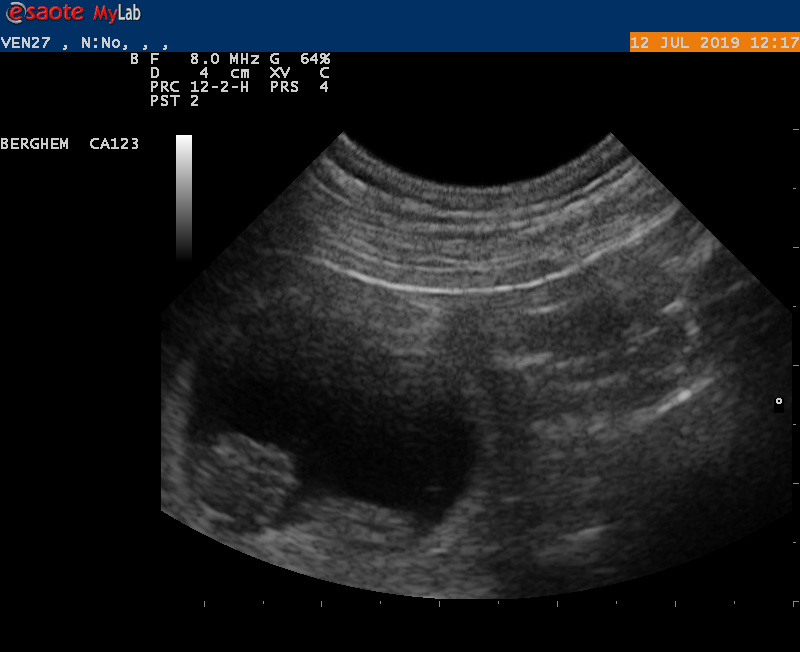

10-6-2021

Vanmiddag zijn we naar de dierenarts geweest met Earke voor een echo. Super goed nieuws: Earke is drachtig. We hebben zelfs al de hartjes zien kloppen van de pups.

Als alles goed blijft gaan krijgen we rond 14 juli een nestje van Earke en Douwe.